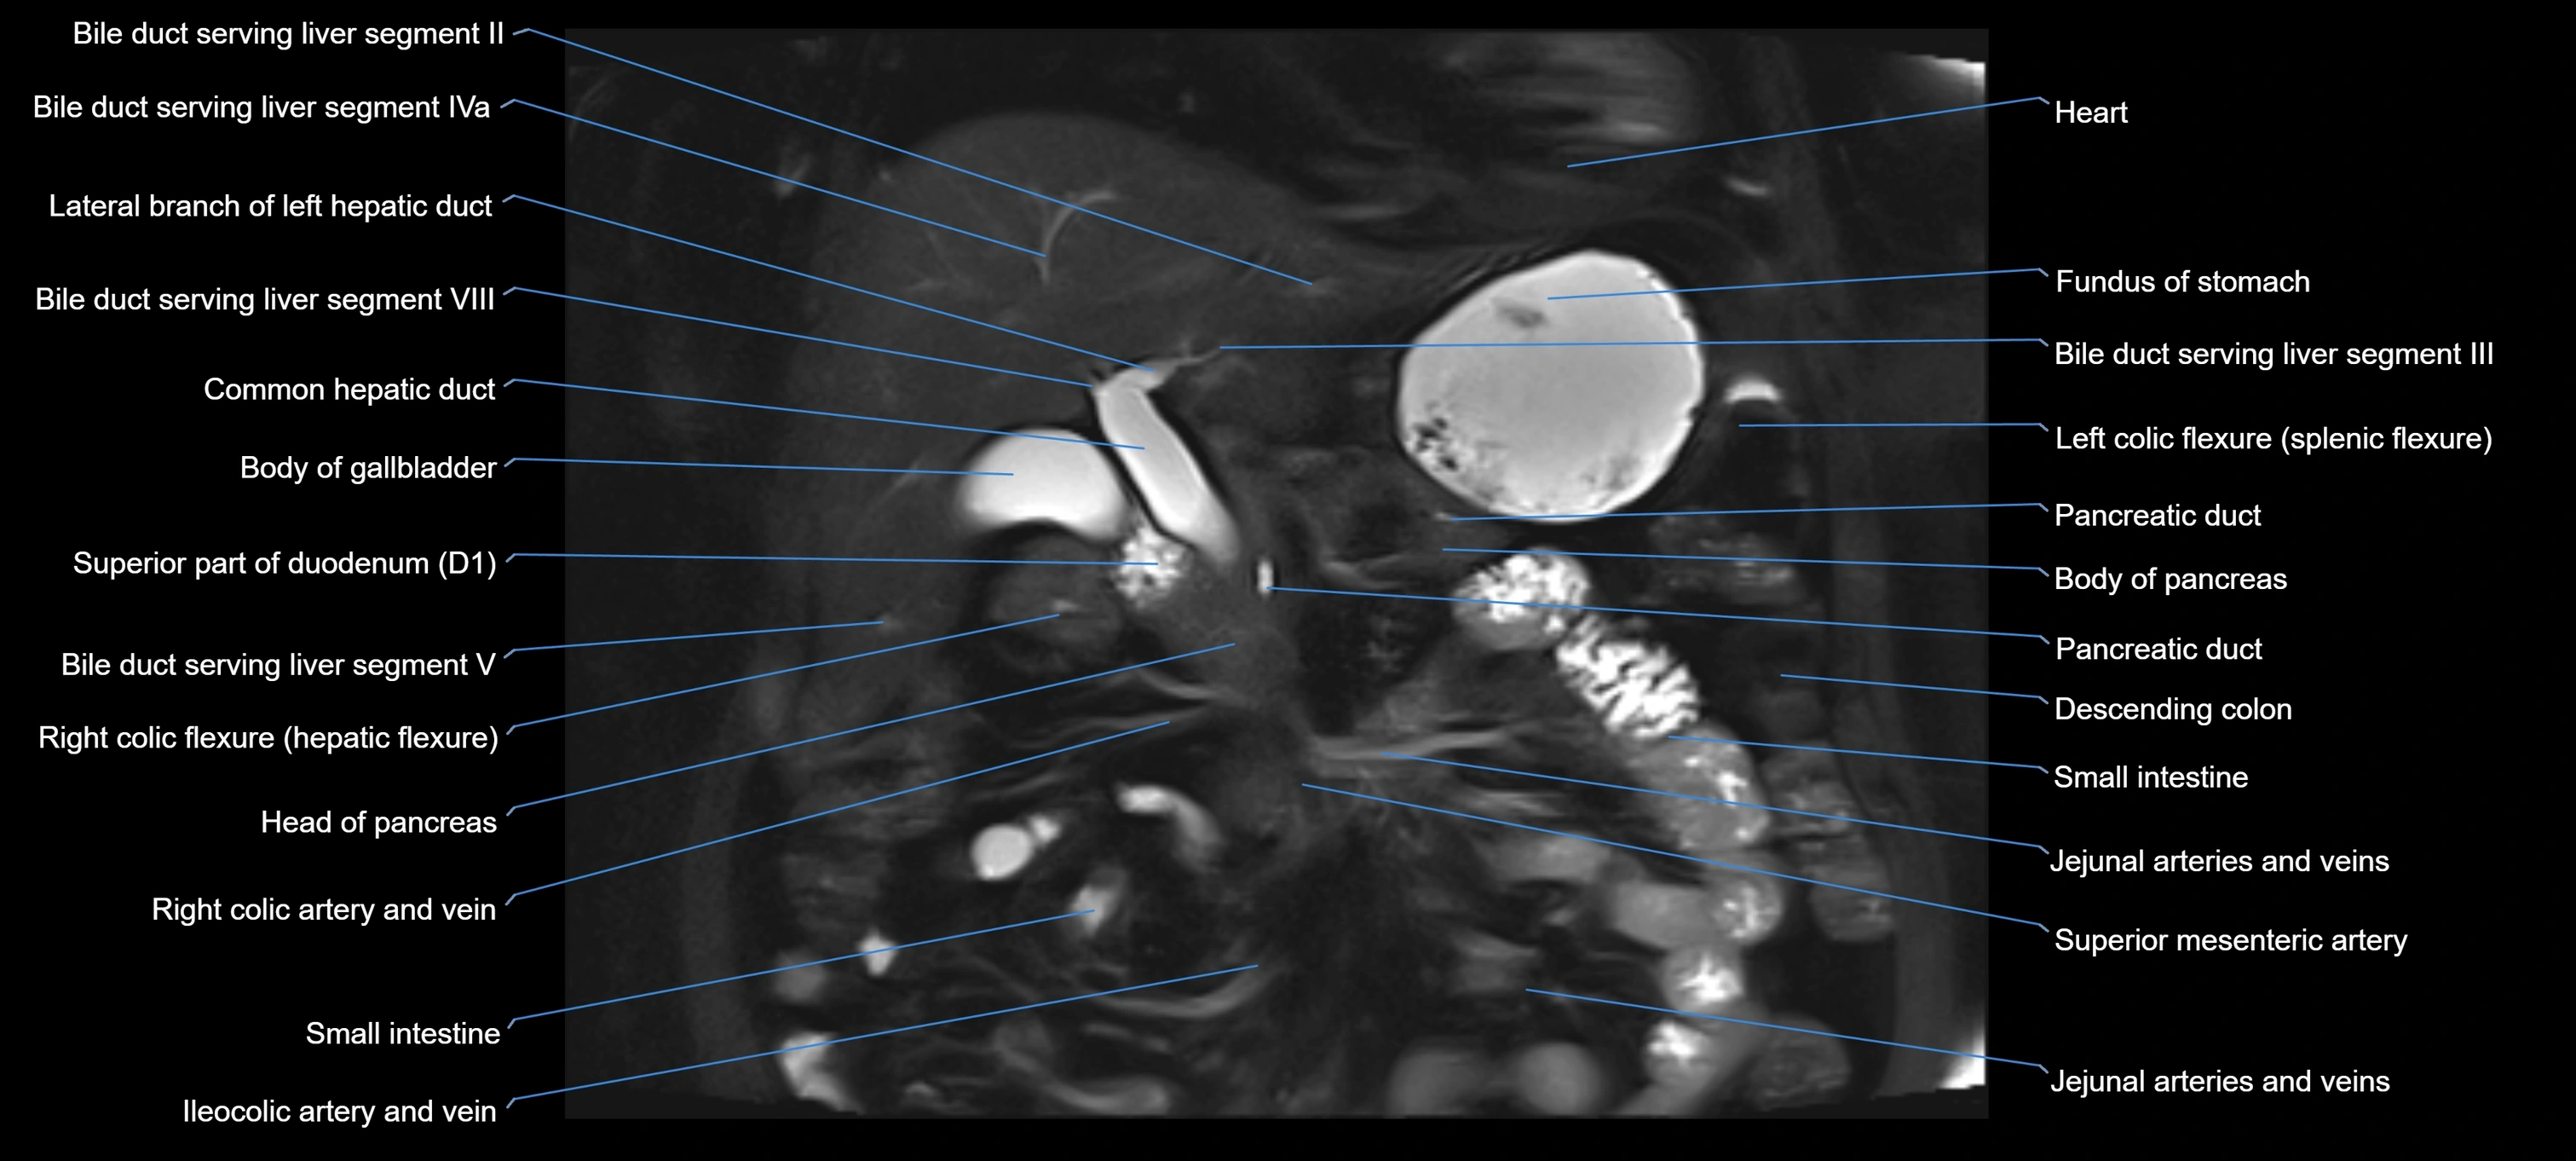

T2 TSE Fat-Saturated 3D (MRCP sequence):

• Duct visualized as a continuous bright tubular structure joining or parallel to the main pancreatic duct

• Allows 3D reconstruction of ductal anatomy and variants

• Excellent for diagnosis of pancreas divisum

Thick-slab T2 Fat-Saturated HASTE:

• Shows the accessory duct as part of the biliary–pancreatic system in a projectional image

• Highlights communication with main pancreatic duct and opening into the minor papilla

• Filling defects (stones, strictures) seen as dark spots within bright fluid

MRI image

image